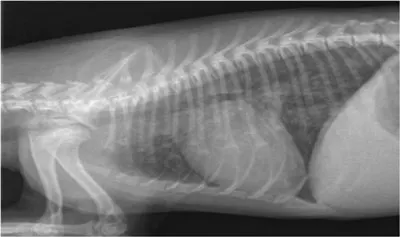

Thoracic radiographs (Figure 1) showed a diffuse bronchointerstitial pattern (reticulonodular). Abdominal radiographs demonstrated generalized hepatomegaly, gas-filled intestinal loops, and poor serosal detail. On abdominal ultrasound, the liver was hypoechoic and the cortices of both kidneys were hyperechoic (Figure 2). Functional ileus was present throughout the gastrointestinal tract.

Figure 1

Note the underlying reticulonodular pattern throughout the lungs evidenced by a generalized increase in soft tissue opacity and multiple linear and circular soft tissue opacities.

Pulmonary Disease

Although relatively uncommon, dogs with leptospirosis may develop dyspnea associated with alveolar hemorrhage. This is a consequence of vasculitis induced by the organism; it manifests radiographically as a coalescing miliary or reticulonodular pattern. Supportive care with oxygen supplementation is often sufficient if the dog shows a rapid response to antibiotic therapy.